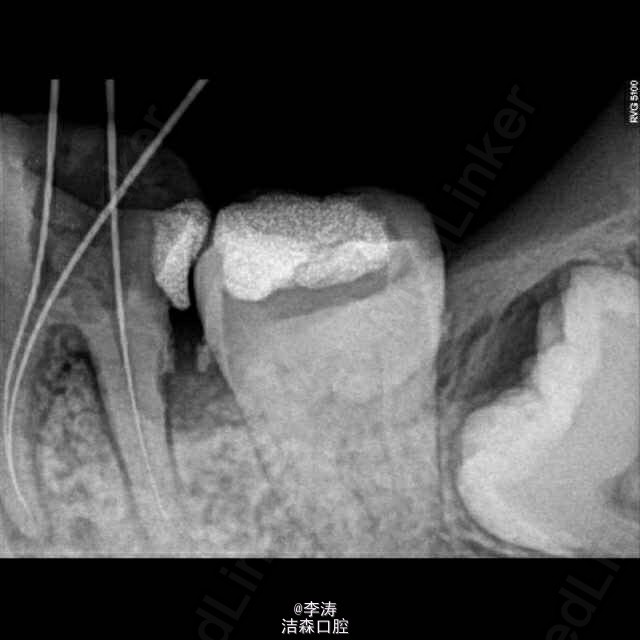

根管预备形成台阶1例

36牙根管治疗,近中根略弯曲,先疏通至15号,k3冠向下法预备,预备时形成台阶,然后怎么预弯都下不去! 太弯根管的还是应该使用手扩,特别是k3,弯曲根管尽量不用,容易形成台阶。另外预备过程中不能使用暴力!!